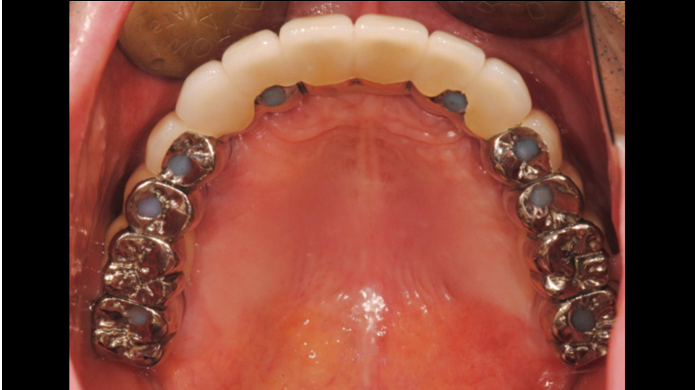

Clinical case: Full-mouth implants for mandibular & maxilla - restored using mixed prostheses

- Courtesy of Dr. Hyun Jun Kim, Korea -

Keywords

AnyRidge, full-mouth implants, mandibular, maxilla, edentulous, full mouth rehabilitation, Octa abutment, long-term clinical case, biological stability, Dr. Hyung Jun Kim

Products:

AnyRidge implant system